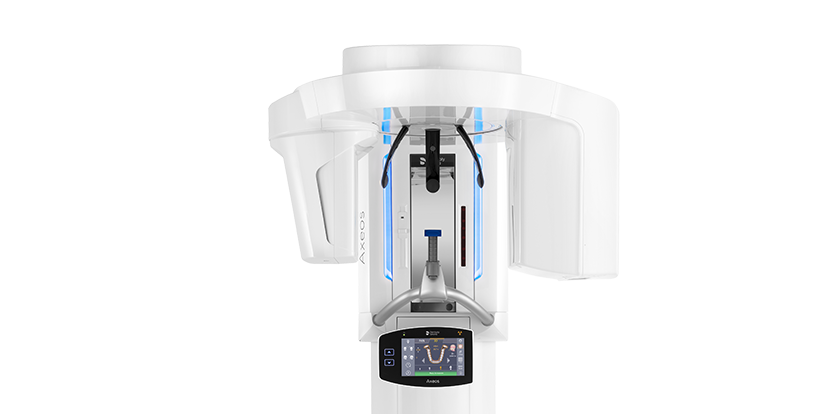

Both the Dentsply Sirona Orthophos® and Axeos® imaging systems are compatible with SureSmile® planning software, allowing providers to communicate records with the SureSmile® Digital lab. Dentsply Sirona’s cloud-based system DS Core® is also a benefit for dentists, as patient files can be easily accessed from anywhere.1 This resource makes it easier for dentists to review treatment plans and make updates as needed through the cloud, even if they are not in the office. It also allows for seamless collaboration between dentists, as files can be easily shared and discussed among colleagues in addition to the SureSmile® Digital Lab.

Patient education and engagement are key components of successful orthodontic treatment and case acceptance, even if it’s an elective procedure. During the initial consultation, be sure to discuss your patients’ individual goals and concerns and tailor the treatment plan to their unique needs. Once a treatment plan is created, the Dentsply Sirona SureSmile® software provides a virtual representation for your patient to preview their predicted treatment outcome. Being able to visualize and fully understand their treatment plan may aid in a higher rate of case acceptance, so that patients will proceed with a provider’s care recommendations. The goal is to provide patients with a positive and empowering orthodontic experience that leads to a healthier, more beautiful smile. With resources like SureSmile® software, Primescan®, Orthophos®, or Axeos® imaging, patients are empowered to make educated decisions and visualize what orthodontic treatment can do for them. This may aid in a higher case acceptance rate, especially given the integration with virtual treatment mapping software at the time of their care planning meeting.

For example, Orthophos® imaging provides a comprehensive view of the patient’s teeth and surrounding structures, enabling dental providers with resources to monitor their patient’s ongoing oral health and ensure that any potential issues are caught early and treated effectively. DS Core®’s accessible cloud-based platforms also allow providers to share records for case plan review, particularly when additional input is needed. With these post-care support options, Dentsply Sirona’s SureSmile® patients can enjoy a beautiful, healthy smile at the completion of their orthodontic therapy, and for years to come.